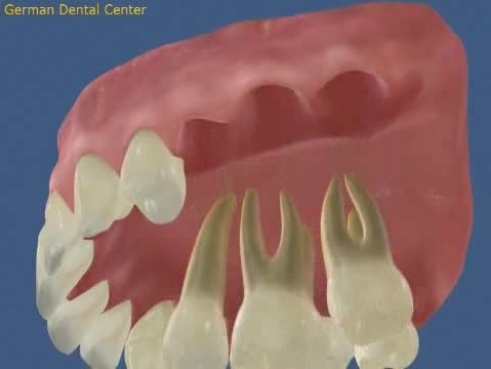

- Имплантация

- Протезирование